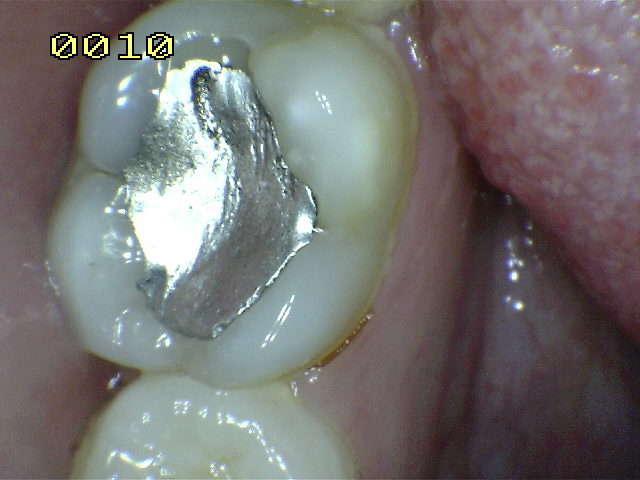

Amalgama de 5 años , observe el desbordamiento por el típico flow de la amalgama en el borde cavo superficial.